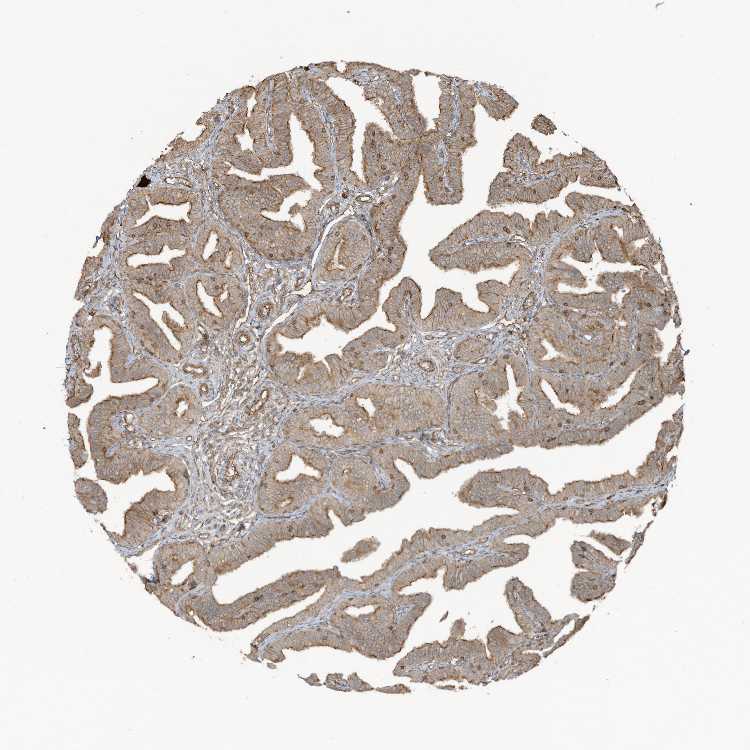

FALLOPIAN TUBE - Antibody stainingi

Antibody staining in the annotated cell types in the current human tissue is reported as not detected, low, medium, or high, based on conventional immunohistochemistry profiling in selected tissues. This score is based on the combination of the staining intensity and fraction of stained cells.

Each image is clickable and will lead to virtual microscopy that enables deeper exploration of all samples and also displays staining intensity scores, fraction scores and subcellular localization as well as patient and tissue information for each sample.

Antibody HPA034507Antibody HPA034508

Glandular cells HighHigh